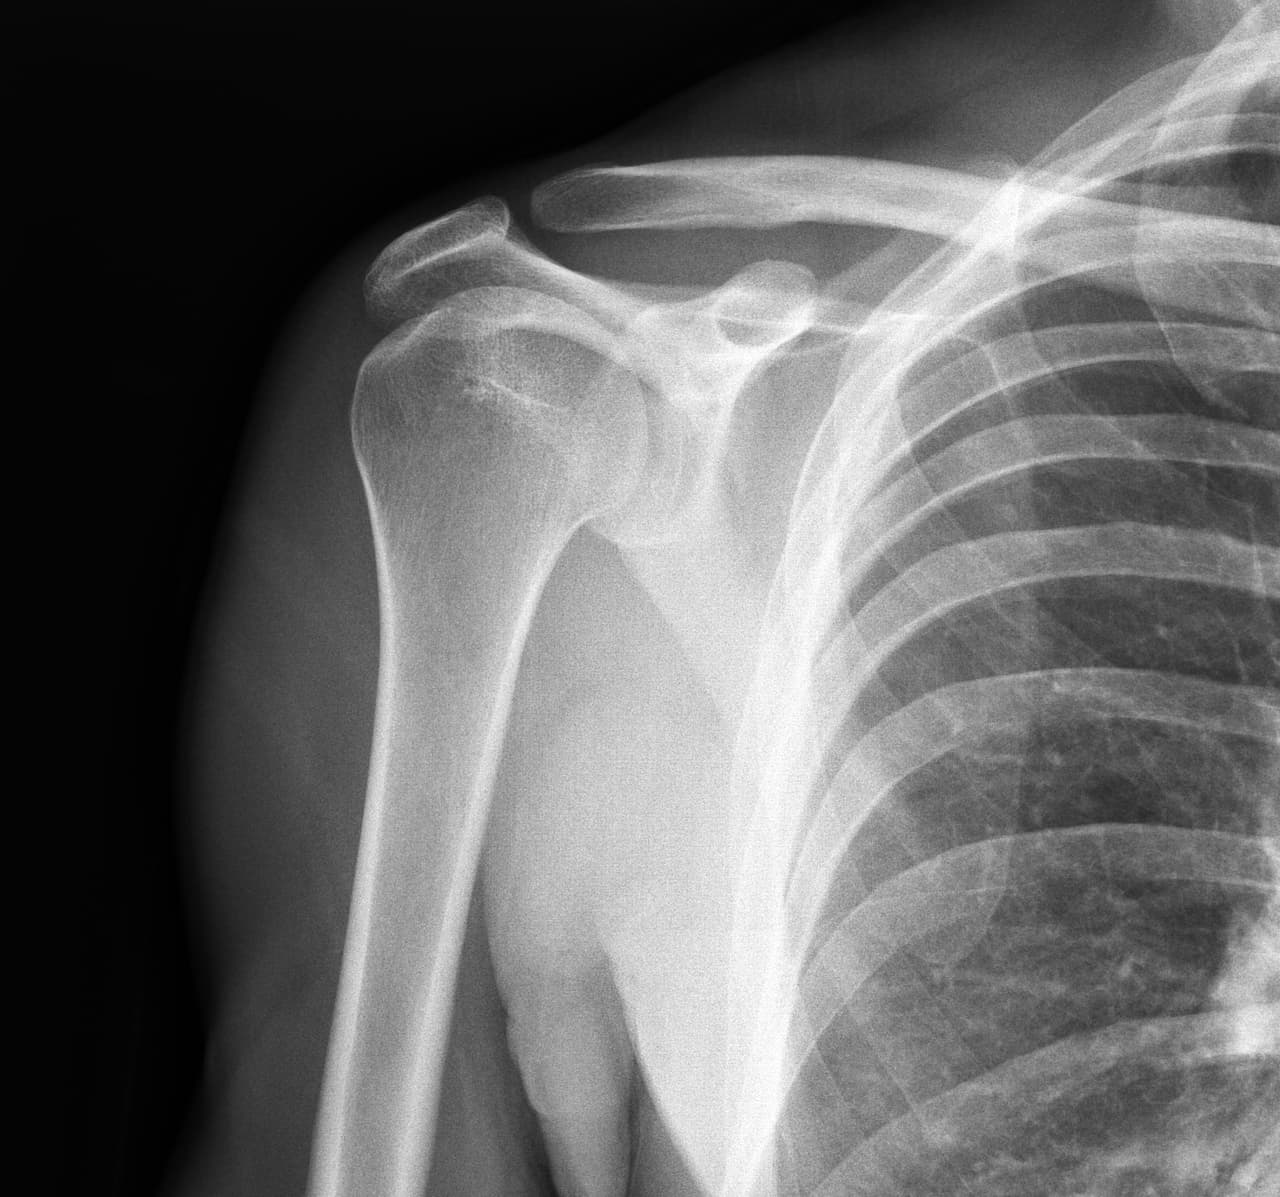

Cuando nos vamos a hacer una radiografía, se suele poner detrás de nosotros una placa sensible a los rayos X, y estos se disparan a través de uno. Los dientes y huesos se ven con mayor claridad porque absorben mayor cantidad de rayos X, al ser más densos.

La radiografía es algo similar a una fotografía pero realizada con rayos X; el fluoroscopio, el mamógrafo y la tomografía computarizada son algunos de los aparatos que utilizan rayos X para el diagnóstico médico.